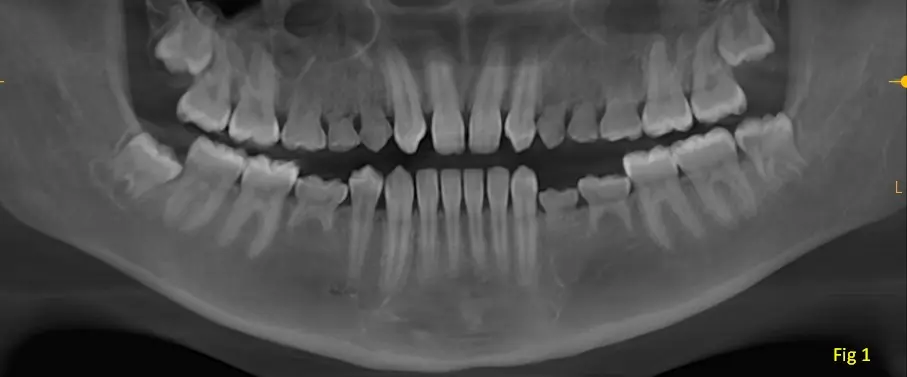

Se presenta el caso de un paciente femenino asintomático, de 15 años de edad que acude al centro de imágenes para la realización de una cone bean indicado por su odontólogo para un control general.

En una vista panorámica (imagen 1) se observa la persistencia de dientes temporarios en zona de premolares en ambos maxilares, tanto en el lado derecho como en el lado izquierdo lo que sugiere un cuadro de agenesia de múltiples piezas dentarias (15-14-12-22-24-25-35-34-45).

Los terceros molares se encuentran en vías de erupción.

Se observa una reabsorción ósea moderada de la cresta alveolar en zonas posteriores del maxilar inferior, específicamente donde hay ausencia de las piezas dentarias permanentes.